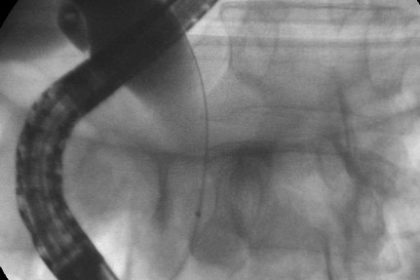

Patient de 51 ans, présentant une abiocholite cactusmeraviglietina.itvaginosisbacteriana.org sur une neo de la tête du pancréas de 22 mm, sans métastase à distance, nécessitant un drainage biliaire pré opératoire.